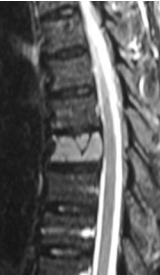

This 43-year-old Caucasian male first presented to a doctor with a complaint of mild thoracic back pain with radiation round the left chest. He had no neurological deficits. X Rays done showed any abnormalities. MRI showed a post contract enhancement in the left half of the T7 vertebra. A CAT guided needle biopsy done was not conclusive. He was then referred for further management, about 5 months after he noticed thoracic backache. Pain was described as a discomfort, occasionally sharp and radiating around the mid left chest. He had no neurological deficits and no myelopathy.

A repeat MRI showed post contrast enhancement of most of T7 vertebra. There was no cord compression.